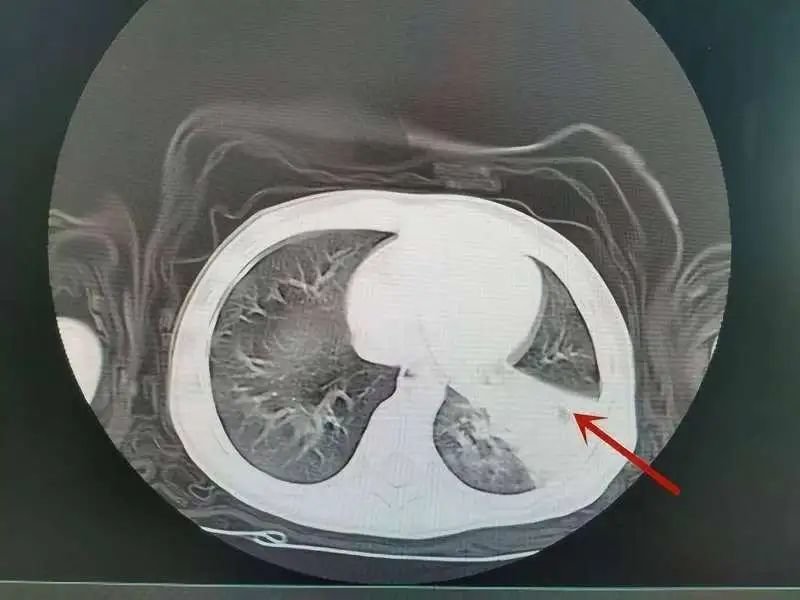

▎图/CT检查显示肺部感染,重症肺炎的图像